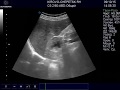

Онкологические болезни в женской половой системе встречаются достаточно часто, одной из самых распространенных патологий данного типа является рак матки, который также называют раком эндометрия или слизистой оболочки матки. В данной статье вы узнаете подробнее о патологии, что это такое, какие первые признаки и симптомы рака, и можно ли его вылечить. Рак тела матки по научному называется карцинома матки или рак эндометрия матки, все это определения одного и того же злокачественного опухолевого процесса, развивающегося во внутреннем эпителиальном слое женского детородного органа. По статистике в России ежегодно о раке матки узнает более 16 тысяч женщин, и с каждым годом эта цифра только увеличивается. В последние десяток лет увеличился процент девушек моложе 30, которые столкнулись с подобной онкологией. В большинстве онкологических заболеваний не возможно точно установить, от чего возникает подобный процесс, это же касается и рака эндометрия.

Причины, лечение и симптомы рака яичников у женщин. Рак яичников и матки считается одной из наиболее частых патологий органов репродукции. Распознать рак матки на ранней стадии проблематично, так как первые симптомы и признаки заболевания себя явно не проявляют. Сколько живут с карциномой матки, зависит от степени опухоли, которая бывает 1, 2, 3, и 4-й. Рак шейки матки чаще всего возникает в возрасте лет. Значительно реже он встречается у молодых женщин. Ежегодно в мире заболевает около полумиллиона женщин.